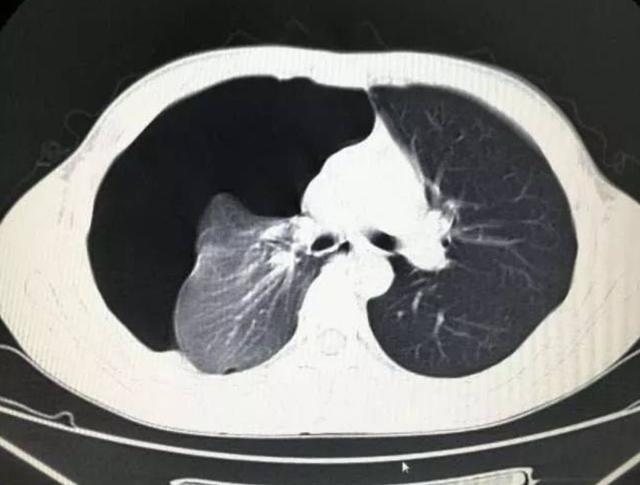

- 危重期:即使吸氧仍呼吸困难,影像学显示白肺

- 高分辨率CT:早期发现毛玻璃样改变